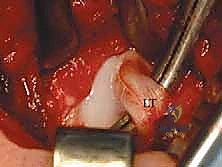

الخطوة 4: تحرير وتر العضلة الحرقفية القطنية (Psoas Tendon Release)

هذا هو أحد أهم أجزاء العملية. وتر العضلة الحرقفية القطنية يكون مشدوداً جداً في حالات DDH ويشكل حاجزاً يمنع رأس الفخذ من النزول إلى مكانه. يقوم الدكتور هطيف بعزل هذا الوتر وقطعه بدقة، مما يزيل الضغط الفوري عن المفصل.

الخطوة 5: فتح الكبسولة المفصلية (Capsulotomy)

بمجرد إزاحة الوتر، تظهر الكبسولة المفصلية بوضوح. يتم إجراء شق دقيق في الكبسولة (غالباً على شكل حرف T أو H) للوصول إلى داخل المفصل.